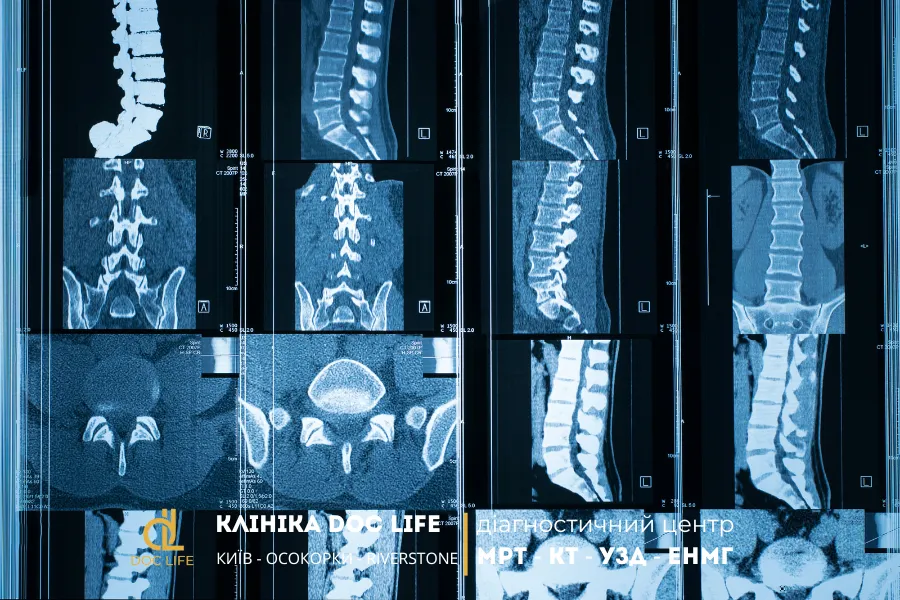

Комп’ютерна томографія хребта (КТ хребта) — це сучасний метод променевої діагностики, який дає змогу отримати надзвичайно точні зображення хребетного стовпа у трьох вимірах. На відміну від звичайного рентгену, КТ створює серію пошарових знімків, що дозволяє лікарю бачити навіть найдрібніші структурні зміни: тріщини, переломи, викривлення, дегенеративні процеси або грижі міжхребцевих дисків.

Принцип дії комп’ютерної томографії полягає у використанні рентгенівського випромінювання, яке проходить через тіло пацієнта під різними кутами. Отримані сигнали обробляються комп’ютером, що формує докладне тривимірне зображення. Завдяки цьому лікар може оцінити стан не лише тіл хребців, а й міжхребцевих суглобів, нервів, судин, а також навколишніх тканин.

Обстеження може проводитися для будь-якого відділу хребта — шийного, грудного або поперекового. У поєднанні з контрастною речовиною комп’ютерна томографія може відобразити навіть найменші судини, що робить цей метод ще точнішим для комплексної діагностики.